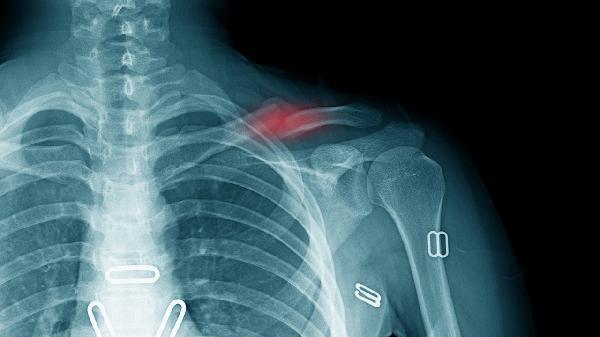

漏斗胸可能导致心脏受压,严重时需3岁后手术矫正;鸡胸多影响外观,少数需胸骨矫形术;胸骨裂罕见但可能危及生命,需新生儿期紧急手术。Nuss手术、Ravitch手术和胸骨翻转术是常见术式。